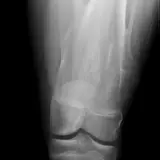

Over 2,100 interactive radiology cases, curated by radiologists for your level of training. Scroll, window, and view cases full screen — just like on PACS. Click linked findings in each writeup to jump straight to them on the image. Cases include sample reports, a focused discussion section, original illustrations, and videos.

PACSで期待されるツールを完備した完全インタラクティブな症例 — スクロール、ウィンドウ調整、ズーム、パン、計測、ROI、フルスクリーンモード。

重要な所見を症例画像上に直接ハイライトする豊富なアノテーション。症例解説内のリンクされた所見をクリックすると、スキャン上の正確な位置へジャンプできます。

職場のPACSステーションと同じようにスクロール、パン、ウィンドウ調整、ズームが可能